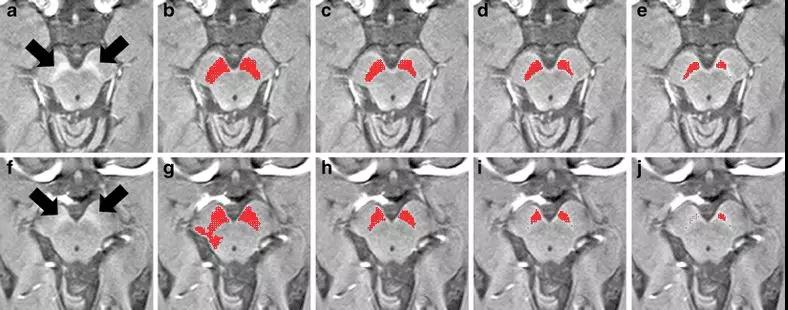

《国家科学院院院刊》中发表的一份报告表示,研究人员已经证明了神经黑色素敏感磁共振信号(NM-MRI)是一种潜在的精神病生物标志物。这项由美国国家卫生研究所心理健康研究所(NIMH)资助的研究发现,NM-MRI信号是精神分裂症患者多巴胺功能的标志,也是精神疾病患者精神症状严重程度的指标。

研究人员表示,“我们现在正在扩展这项工作,看看我们是否能够检测到神经黑色素信号的异常,这些异常有助于我们预测在那些已经表现出精神病早期症状的人群中,那些人可能发展出精神症失常。我们也有兴趣探索在将来,神经黑色素敏感的磁共振信号是否可以用于确定谁最能从多巴胺治疗中受益。”